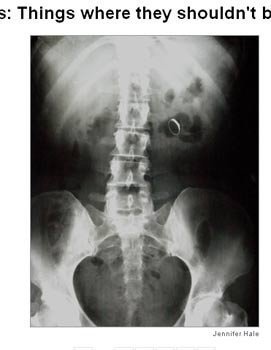

Hai trường hợp trên, các bác sĩ đã để quên kéo trong bụng của bệnh nhân sau khi phẫu thuật. Trường hợp thứ hai, trong cơ thể bệnh nhân có tới 2 cái kéo.